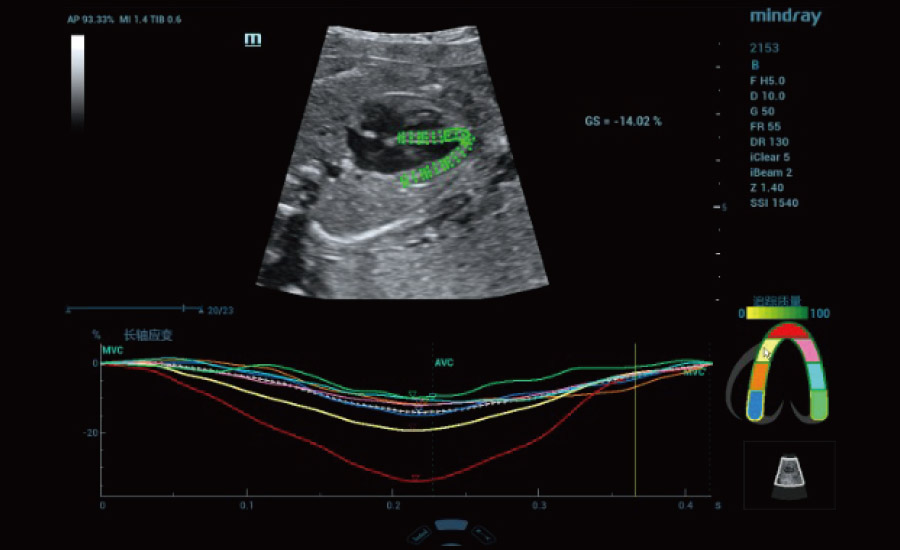

UMA (angiografia ultramicroscĆ³pica)

A tecnologia inovadora elimina as limita??es das tradicionais imagens com Doppler. Com resolu??o espacial e sensibilidade de fluxo ultra-altas, permite a detec??o de perfus?es de fluxos muito sutis e lentos, ampliando assim a aplica??o clĆnica da avalia??o qualitativa e quantitativa do ultrassom no cĆ©rebro fetal, rins, placentas, endomĆ©trios, ovĆ”rios etc.

Informa??es abrangentes adaptadas aos cenƔrios

Por meio da combina??o de algoritmos avan?ados e do conhecimento especĆfico da regi?o, a inovadora solu??o Smart Scene permite a identifica??o automĆ”tica das caracterĆsticas do tecido e fornece diagnĆ³stico especĆfico dos Ć³rg?os com informa??es completas. Com base na identifica??o automĆ”tica de cenĆ”rios, a solu??o realiza n?o apenas a varredura 2D inteligente com configura??es e medidas automĆ”ticas, mas tambĆ©m oferece informa??es 3D abrangentes em todas as etapas, desde a otimiza??o de imagens volumĆ©tricas atĆ© a difĆcil obten??o de planos 2D, e a quantifica??o durante todo o procedimento. Ele ajuda a reduzir em grande parte a dependĆŖncia de habilidades clĆnicas, ao mesmo tempo que aumenta a precis?o, a confian?a e a eficiĆŖncia no diagnĆ³stico.